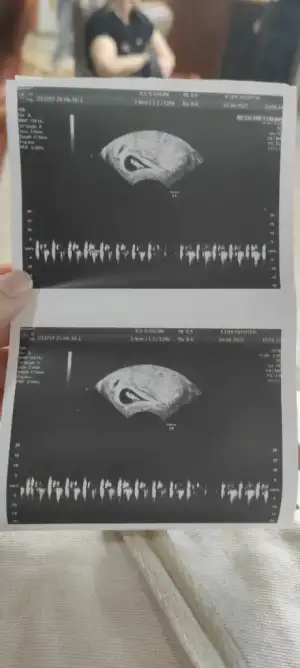

Ay çok merak ediyorum bizede bakar mısınız karından ultrason ile bakıldı görsellerde ilk görsel 10+4 diğer görseller 6+4 haftalıkken bir oğlum var bide kızımız olur inşallah :)Kızlar 6-8 haftalık ultrason görüntülerinizi atın tahmin yapalım . Ya da cinsiyeti öğrenen annelerimiz 6-8 haftalık görüntülerini atsın bize de fikir olsun

Yok karindan ultrasonBir oğlum var kızım olmasını da isterimsizinde Vajinal ultrason görüntüsümüydü

Umarım kızınız olur ama bence bebeğiniz erkekAy çok merak ediyorum bizede bakar mısınız karından ultrason ile bakıldı görsellerde ilk görsel 10+4 diğer görseller 6+4 haftalıkken bir oğlum var bide kızımız olur inşallah :)